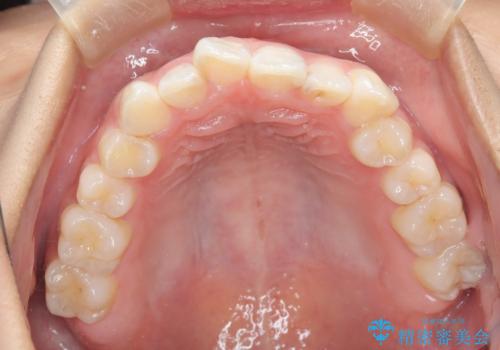

- 前歯の叢生(がたつき)を主訴に来院された患者様です。以前マウスピース矯正をされていたそうでしたが、自身での継続が難しいことなどを理由に、ワイヤー矯正にて改めて矯正治療を希望されました。非抜歯にて治療を計画し治療を行いました。

歯の動きが良く、スムーズに治療を終了しました。一般的にワイヤー矯正はブラッシングが難しいのですが、毎回一生懸命セルフケアをされていたのが印象的です。治療においては、歯の衛生状態も一緒にチェック致します。